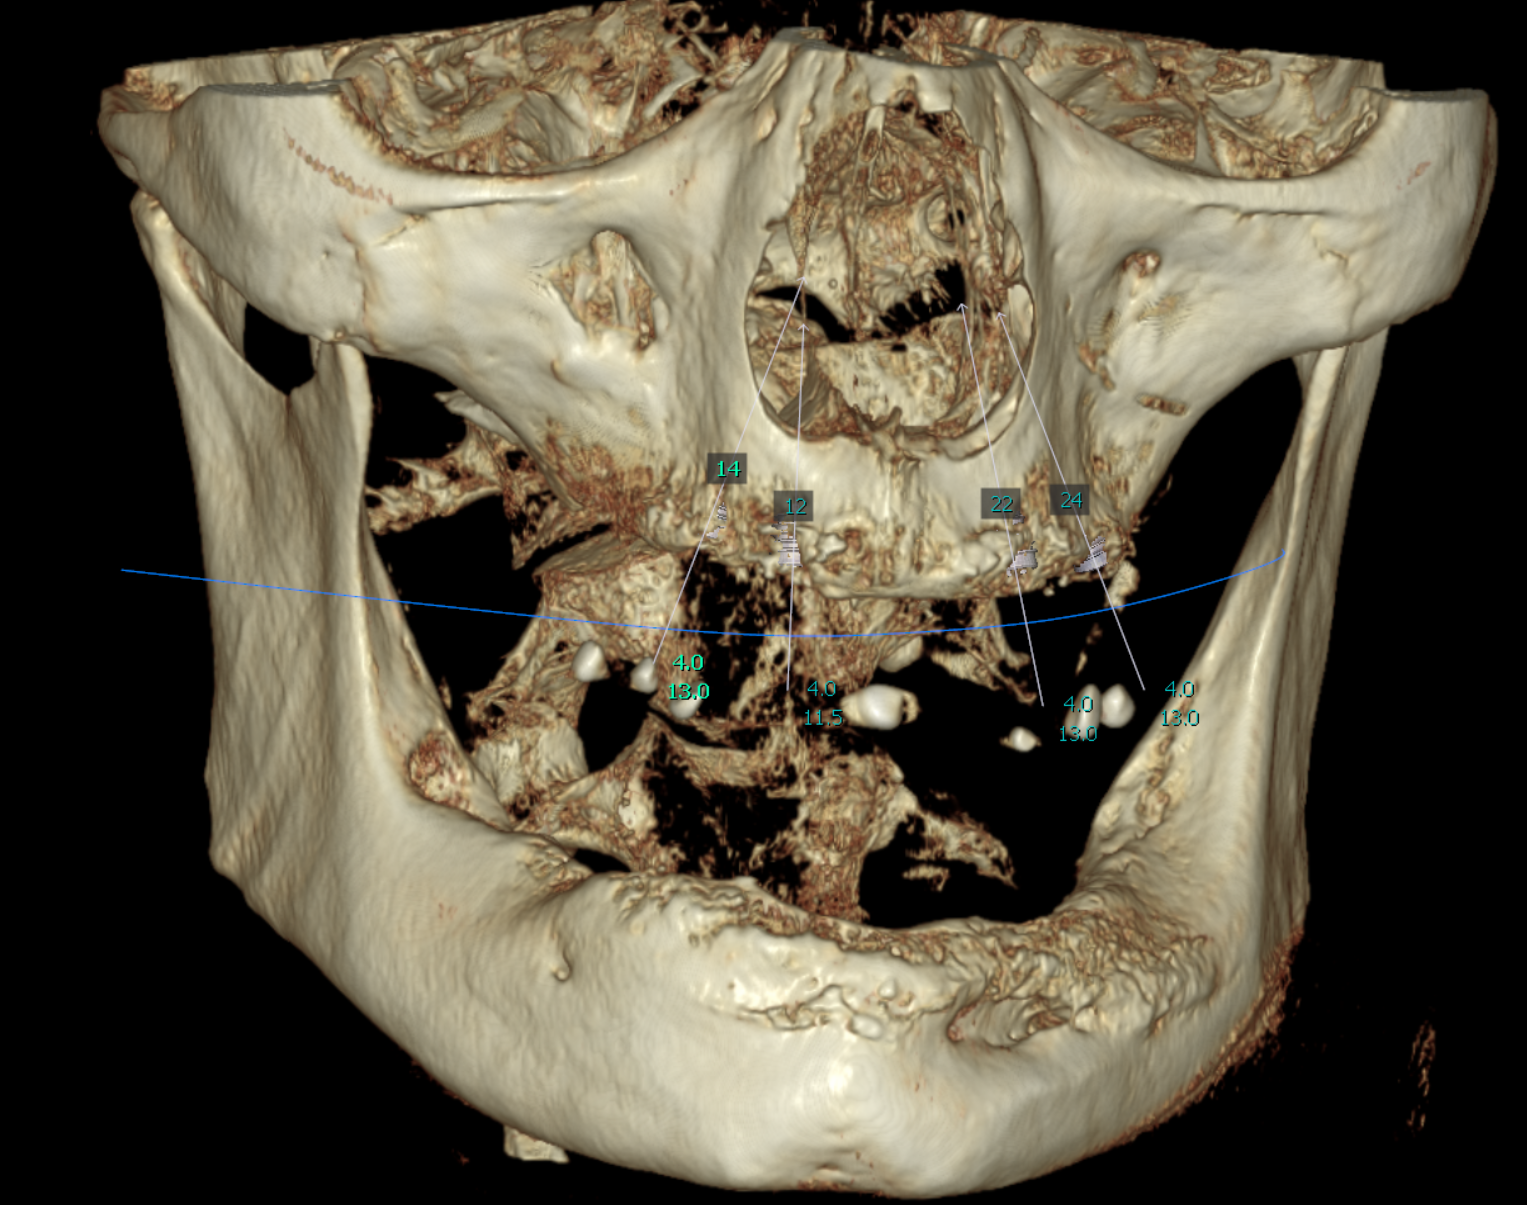

Cone Beam Computed Tomography (CBCT) scans were acquired for both the maxillary and mandibular arches. These scans provided critical insights into available bone volume, bone density, and anatomical considerations, forming a foundation for precise implant planning and guided surgery.

Bone was measured to asses the amount of bone gained and the density of the said bone and also a first simulation of implant placement was performed.

Implant placement planning done in EXOPLAN involved careful digital matching of the CBCT, wax-up, and facial scan data, resulting in an accurate, digitally-produced try-in prosthesis (Fig. 8). The validated prosthetic design was subsequently integrated with the software to plan placement of five strategically positioned implants in the upper arch.